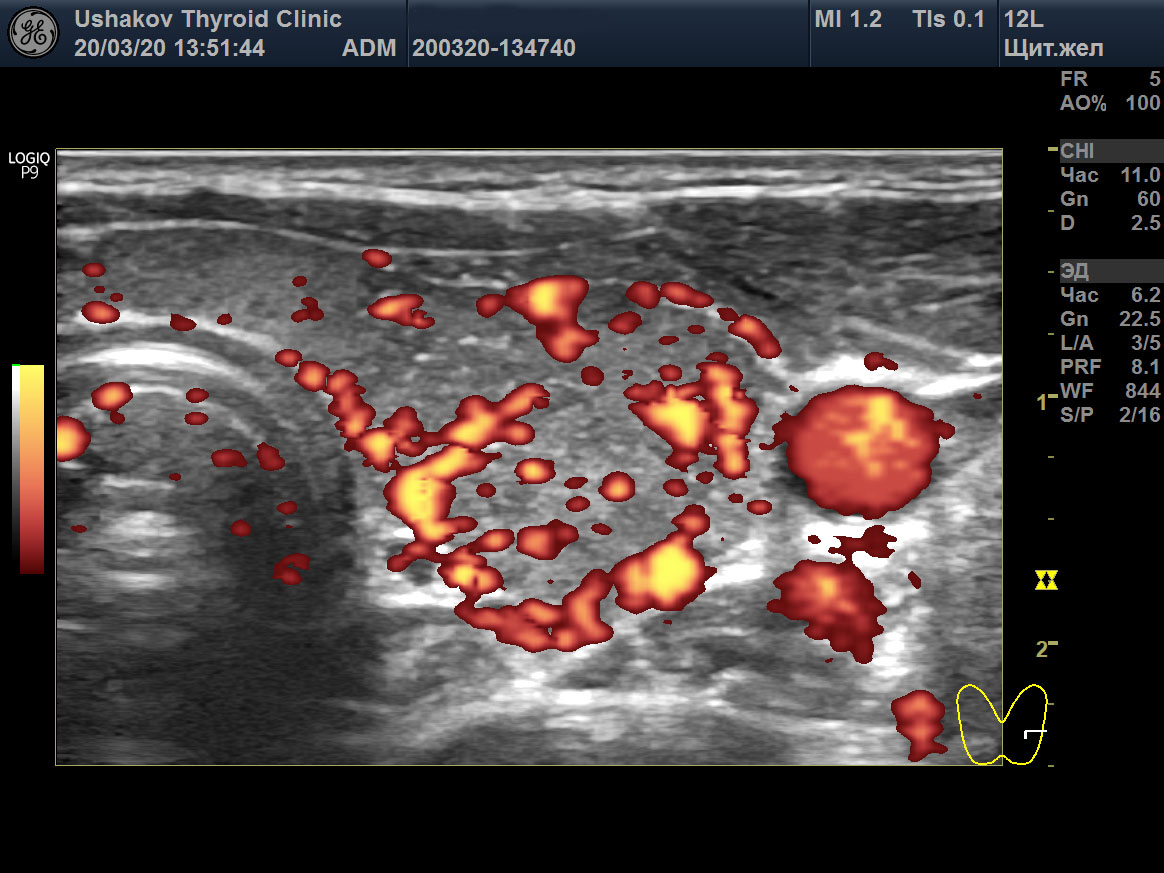

Пример такого случая представлен на

снимках ниже, где показаны две доли ЩЖ пациентки 31 года в режиме ЭДК и ПССК в системе верхних щитовидных артерий (ВЩА). Интенсивность кровотока при ЭДК усилена до значительной степени, а ПССК – до умеренно избыточной величины (норма 20-30 см/с [127]).

Рисунок 1 Левая и правая доли ЩЖ пациентки 31 года (поперечные и продольные проекции в режиме ЭДК; ПССК в режиме ЦДК), УЗИ 20.03.2020. Объём ЩЖ 9,1 мл (рост 170 см, масса 50 кг). Данные анализа крови от 18.03.2020: ТТГ 33,6 мЕд/л [0,4-4,0], Т4св. 6,7 пмоль/л [9,0-19,0], Т3св. 4,1 пмоль/л [3,0-5,6], АТТПО >1000 Ед/мл [<5,6], АТ-ТГ 368,8 Ед/мл [<18]. ПССК в системе ВЩА слева и справа 54 см/с. Концентрация йода в моче 200 мкг/л. Медикаменты не принимает продолжительный период.

Рисунок 1 продолжение

Рисунок 1 окончание |

В результате при обращении в нашу Клинику были выявлены признаки значительного перенапряжения ЩЖ по данным УЗИ в виде значительной интенсификации тиреоидного кровотока (

рис. 1). Эта избыточная стимуляция ЩЖ со стороны гипофиза (ТТГ 33,6 мЕд/) и периферической ВНС, тем не менее, сопровождалась